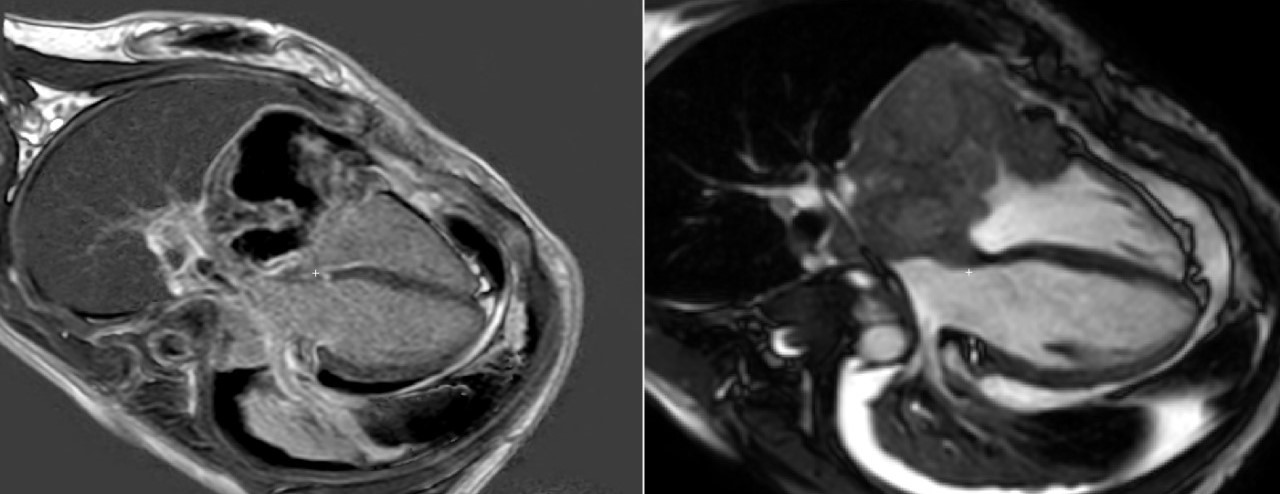

Image 2: Left: PSIR sequence 10 minutes after contrast injection in four chambers view showing heterogeneous enhancement with a central area of null signal suggesting avascular region. Right: 4 chambers BSSFP cine sequence showing typical cauliflower-like appearance plus residual pericardial and pleural effusion..jpg)